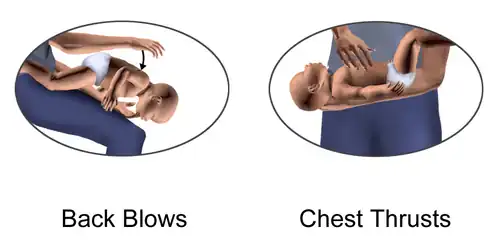

First aid for choking infants alternates a cycle of special back blows (five back slaps) followed by special chest thrusts (five adapted chest compressions).

In the back blows maneuver, the rescuer slaps on the baby's back. It is recommended that the baby receive them being slightly leaned upside-down on an inclination. There exist several ways to achieve this:

According to a widely propagated modality: the rescuer sits down on a seat with the baby, and supports the baby with a forearm and its respective hand. The baby's head must be carefully held with that hand (approximately by the face), and kept in a normal position, facing forward, not inclinated. Then the baby's body can be leaned forward upside-down along the rescuer's thighs, and receive the slaps.

As an easier alternative: the rescuer can sit on a bed or sofa, or even the floor, carrying the baby. Next, the rescuer should support the baby's body on the own lap, to lean the baby a bit upside-down at the right or the left of the lap. The baby's head must be in a normal position, facing forward, frontally, and not inclinated. It is always convenient that the baby's chest is supported against something. Then the rescuer would slap the back of the baby.

If the rescuer cannot sit down: at least it is possible to attempt the manoeuver at a low height and over a soft surface. Then the rescuer would support the baby with a forearm and the hand of that side, holding carefully the baby's head with that hand (approximately by the face, but always trying that the baby's head keeps in a normal position, facing forward, not inclinated). The baby's body would be leaned upside-down in that position to receive the slaps. In situations with rescuers who cannot do all of that (as rescuers with disabilities and others), they can still try the normal back blows, supporting the baby's chest with one hand, bending the baby's body, and then giving firm slaps with the other hand.

In the chest thrusts manoeuver, the baby's body is placed lying face up on a surface (it can be the rescuer's thighs, lap or forearm). Then, the rescuer does the compressions pressing with only two fingers on the lower half of the bone that is along the middle of the chest from the neck to the belly (on the chest bone, named sternum, on its part that is the nearest to the belly). Abdominal thrusts are not recommended in children less than one year old because they can cause liver damage.[60]

The back blows and chest thrusts are alternated in cycles of five back blows and five chest compressions until the object comes out of the infant's airway or until the infant becomes unconscious.[60]